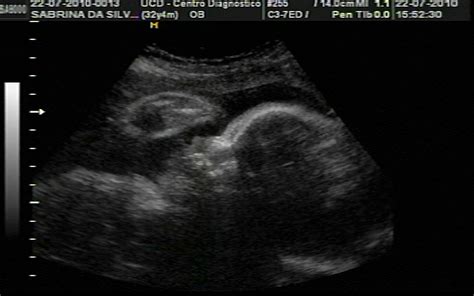

Ecografia 32 Semanas De Embarazo, , , , , , , 0, Ecografia 4D embarazo de 32 semanas cara 4D - YouTube, www.youtube.com, 1280 x 720, jpeg, WebLa ecografía de semana 32 tiene como principal finalidad comprobar que el feto crece bien. Además, permite valorar el bienestar fetal en tercer trimestre. En las gestaciones. WebLos percentiles y el crecimiento del bebé. Durante la ecografía de las 32 semanas, el médico evaluará el percentil en el que se encuentra tu pequeño. Para ello, medirá. WebSe llama Ecografía de Crecimiento Fetal y se efectúa habitualmente a caballo entre las 28 – 32 y las 35- 37 semanas de gestación. Además de esto, de volver a repasar la., 20, ecografia-32-semanas-de-embarazo, Novedades y Muebles WebLa ecografía de semana 32 tiene como principal finalidad comprobar que el feto crece bien. Además, permite valorar el bienestar fetal en tercer trimestre. En las gestaciones. WebLos percentiles y el crecimiento del bebé. Durante la ecografía de las 32 semanas, el médico evaluará el percentil en el que se encuentra tu pequeño. Para ello, medirá. WebSe llama Ecografía de Crecimiento Fetal y se efectúa habitualmente a caballo entre las 28 – 32 y las 35- 37 semanas de gestación. Además de esto, de volver a repasar la.

WebDurante la semana 32 de embarazo el bebé pesará aproximadamente 1,7 kg y medirá casi 30 cm. Su tamaño será similar al de una col china. Echa un vistazo a esta imagen para. WebEcografía Semana 31 – Semana 32. En la semana 31 de embarazo la piel de tu bebé está más rosada porque ha aumentado la acumulación de grasa subcutánea. Pesa entre. WebSemana 32 de Embarazada Es un buen momento para realizar la ecografía de tercer trimestre en la que se cuantifica el líquido amniótico del bebé, se repasa su morfología y. WebA partir de la semana 36 de gestación (32 si es múltiple y sin complicaciones) la recomendación es no volar, pero puedes acceder con un certificado de tu médico en el. WebLas tres ecografías del embarazo. En un embarazo normal o de bajo riesgo se recomienda realizarse tres ecografías, una por trimestre. La primera entre las semanas 11 y 14, la.

WebEl examen revela el bienestar fetal y anticipa problemas del parto. La ecografía del tercer trimestre de embarazo se realiza entre la semana 32 y 36 y valora el tamaño del bebé y. WebSe denomina Ecografía de Crecimiento Fetal y se realiza habitualmente a caballo entre las 28- 32 y las 35- 37 semanas de gestación. Además, de regresar a comprobar la. WebLa ecografía doppler fetal es una técnica de imagen habitual en obstetricia para examinar el corazón y los vasos sanguíneos del feto, especialmente importante a las.

WebLas tres ecografías del embarazo. En un embarazo normal o de bajo riesgo se recomienda realizarse tres ecografías, una por trimestre. La primera entre las semanas 11 y 14, la. WebLa tercera ecografía se realiza entre las semanas 32 y 36 de embarazo. Es probablemente la última ecografía antes del nacimiento del bebé, por lo que sirve.